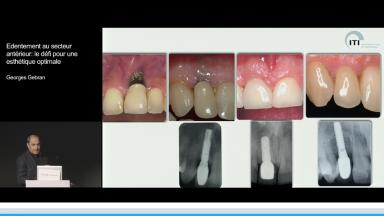

Edentement au secteur anterieur: le défi pour une esthetique optimale

A partir de la description des facteurs de risque esthétique du bloc incisivo-canin maxillaire, de la présence d’os et de gencive autour des implants, le conférencier présente une succession de cas cliniques décrivant ses procédures chirurgicales et prothétiques.